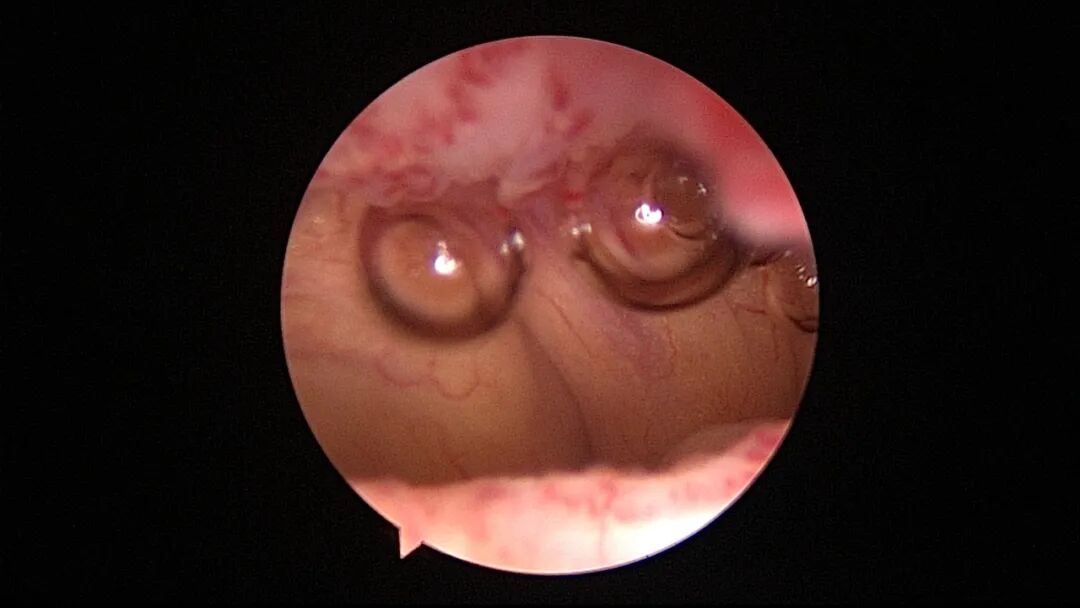

尽量保护输卵管开口周围内膜不受损伤,术中仅显露出左侧输卵管开口。该患者术后自然妊娠,34+周剖宫产分娩